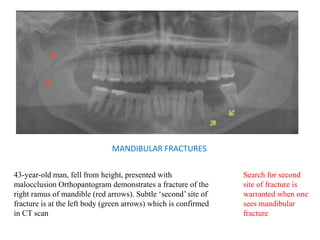

MANDIBULAR FRACTURES

43-year-old man, fell from height, presented with

malocclusion Orthopantogram demonstrates a fracture of the

right ramus of mandible (red arrows). Subtle ‘second’ site of

fracture is at the left body (green arrows) which is confirmed

in CT scan

Search for second

site of fracture is

warranted when one

sees mandibular

fracture